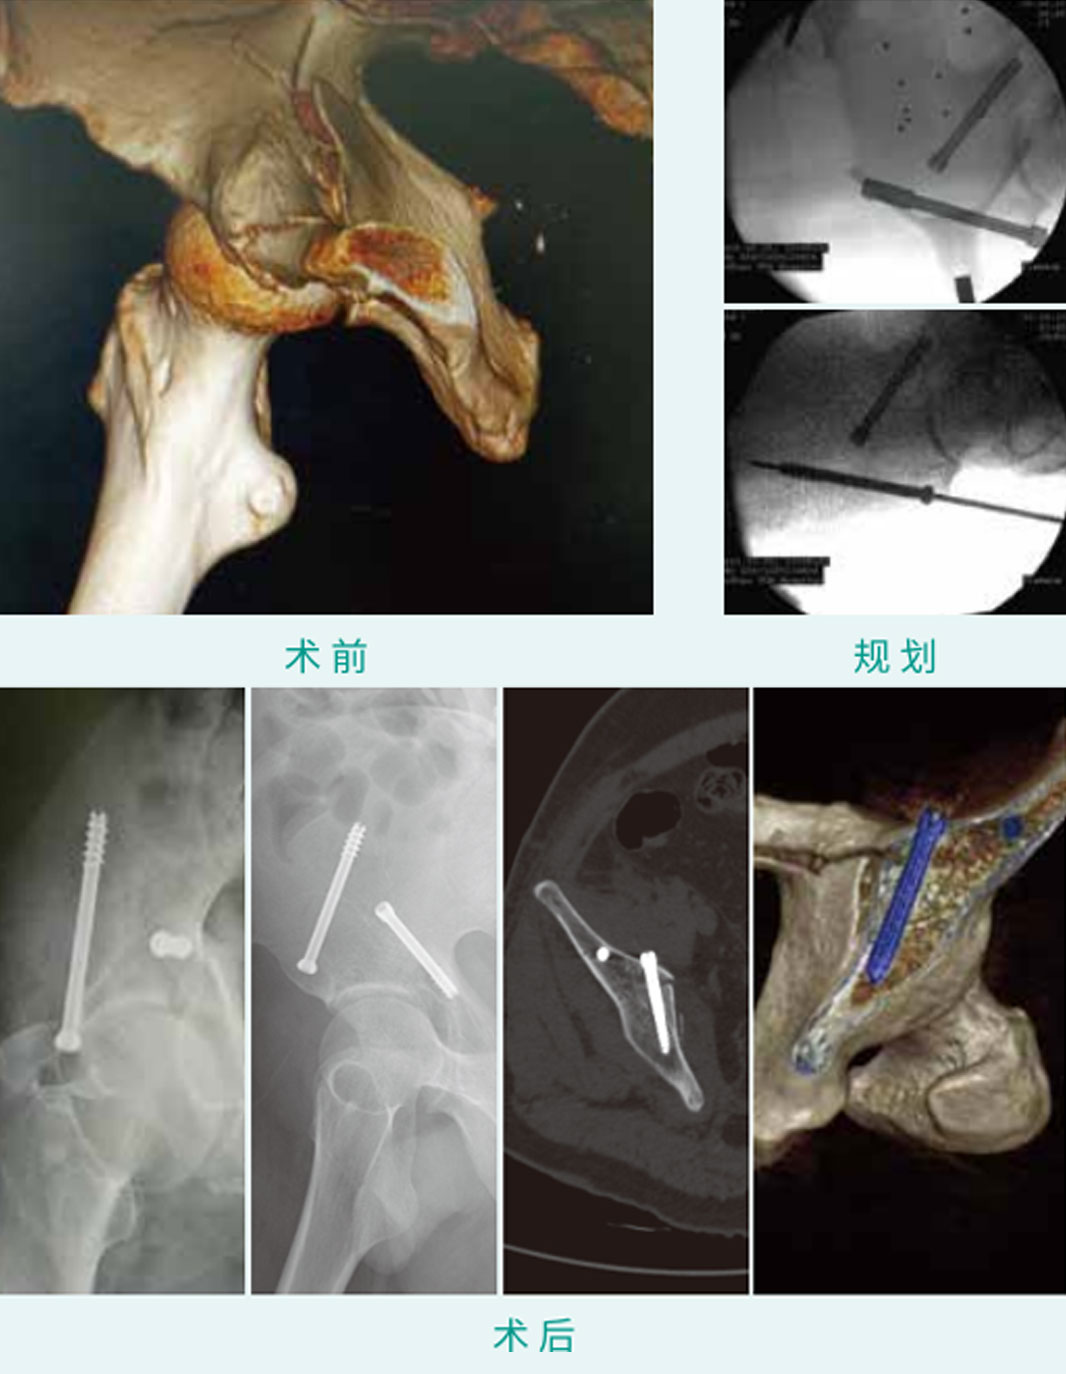

天玑? 辅助骨盆“Magic”螺钉LC-2螺钉内牢靠术

基本情形:患者男,,,,,,53岁,,,,,,骨盆髋臼骨折

机械人累积用时:25分钟

植入物:2枚空心螺钉

病例泉源:佛山市中医院 吴征杰 陈国涛